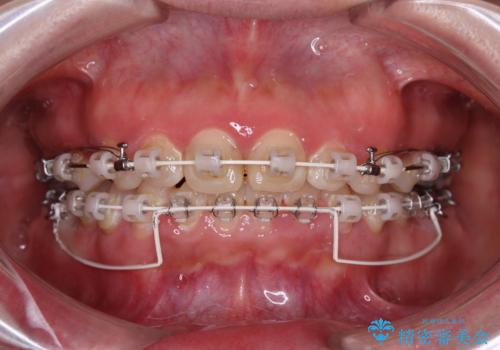

- 矯正装置

- 審美装置

骨格的に上顎が前方にあり、上顎のみの抜歯矯正のため、期間はかかることが予想されましたが、スムーズに移動してくれたおかげで、2年弱の短期間で終えることができました。